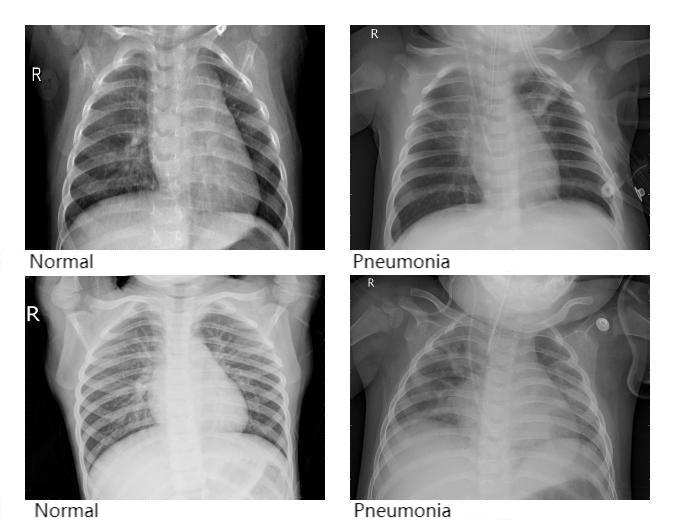

Because pneumonia incidence remains high and traditional diagnostic methods face efficiency bottlenecks, and since convolutional neural networks are increasingly applied in medical image analysis, this paper employs the AlexNet model to analyze chest X-ray images for pneumonia detection. The study optimizes the training process by tuning the number of epochs to identify the model with the best accuracy. Experimental results show that the model achieved an accuracy of 0.8108 (81.08%), demonstrating good capability for recognizing pneumonia in X-ray images. This method can help reduce the bias and time required by manual interpretation, effectively improve the efficiency of pneumonia screening, and gain valuable time for timely diagnosis and treatment.